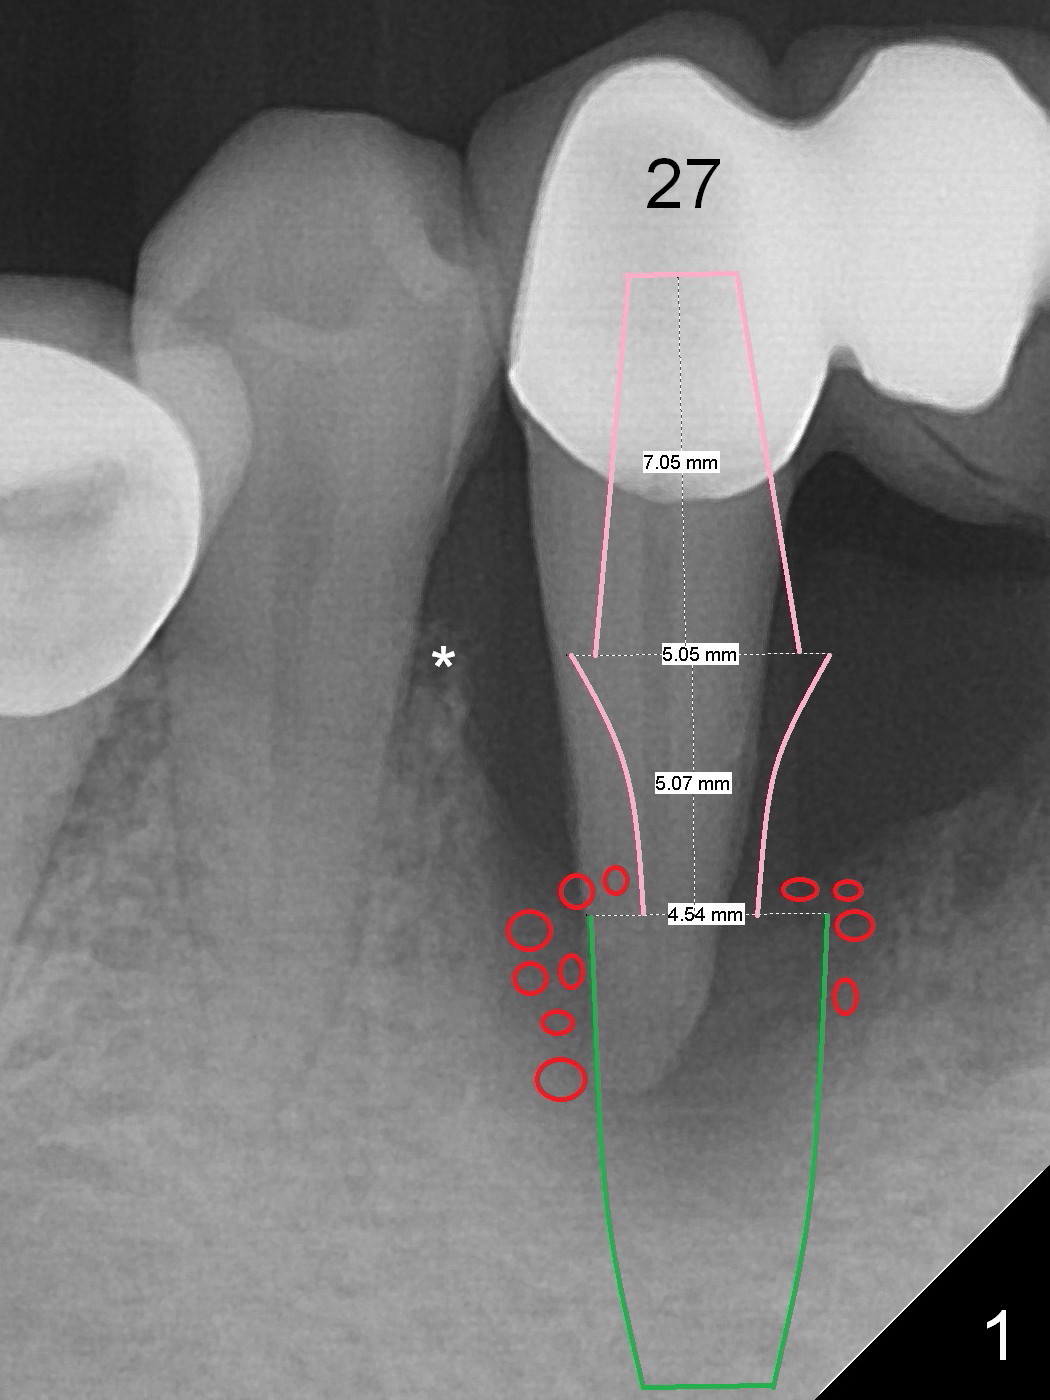

A 57-year-old woman has a 20-year-old loose FPD (fixed partial denture, Fig.1-3).  Upon Alginate impression for stent, the 6-unit FPD was dislodged with the exfoliated abutment at #27.  After removal of calculus from the root of #27, the FPD was placed in situ and temporarily cemented to #22 abutment.  When the patient returns, remove the FPD, treat the socket of #27 with Clindamycin, place implants at #23, 25 and 27 and fabricate a 6-unit provisional FPD.  At definitive stage of restoration, fabricate a 4-unit FPD at #24-26 and a single unit at #27.  Since bone loss is more severe mesiobuccally at #27 (Fig.1), place an implant as lingual as possible, but slightly more mesially.  If the defect is so severe that the implant (green) has to be placed deep, the abutment margin with the longest cuff (5 mm, pink) is less likely to contact the distal crest (*).  Crown margin (i.e., abutment margin of an implant) should be 2 mm more coronal to the crest normally.  The condition that does not meet the requirement is called violation of biologic width, associated with periodontitis or periimplantitis.